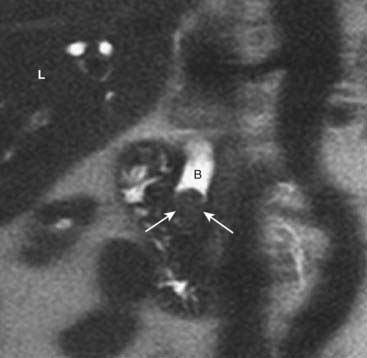

Biliary System: Magnetic Resonance Cholangiopancreatography (MRCP)

image MRCP (magnetic resonance cholangiopancreatography) is a noninvasive way to image the biliary tree without requiring injection of contrast material. MRCP utilizes MRI imaging sequences that make fluid-filled structures like the bile ducts, pancreatic ducts and gallbladder extremely bright, and everything else dark. Patients are imaged during a single-breath hold.

image MRCP is excellent at depicting biliary or ductal strictures, ductal dilatation, stones in the bile ducts (choledocholithiasis), gallstones, adenomyomatosis of the gallbladder, choledochal cysts, and pancreas divisum.

image If there is a concern for malignancy (such as pancreatic adenocarcinoma or cholangiocarcinoma) as the cause of pancreaticobiliary ductal dilatation, then additional pulse sequences following the administration of gadolinium can be obtained. Contrast administration allows better detection of malignancy (Fig. 18-36).

image

Figure 18-36 Choledocholithiasis and biliary ductal dilatation on magnetic resonance cholangiopancreatography (MRCP).

This is a coronal close-up of the right upper quadrant utilizing MR imaging. There is a large obstructing gallstone (solid white arrows) in the distal common bile duct (B), which is dilated to 13 mm. Because of the signal characteristics of bile, an MRCP can be done without the need for the injection of contrast. (L = liver.)